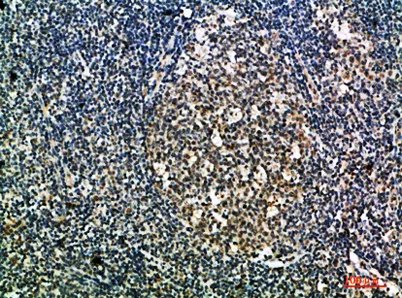

- Validated Applications: IHC, IF, ELISA

- Dilution: IHC-p 1:50-200, ELISA 1:10000-20000